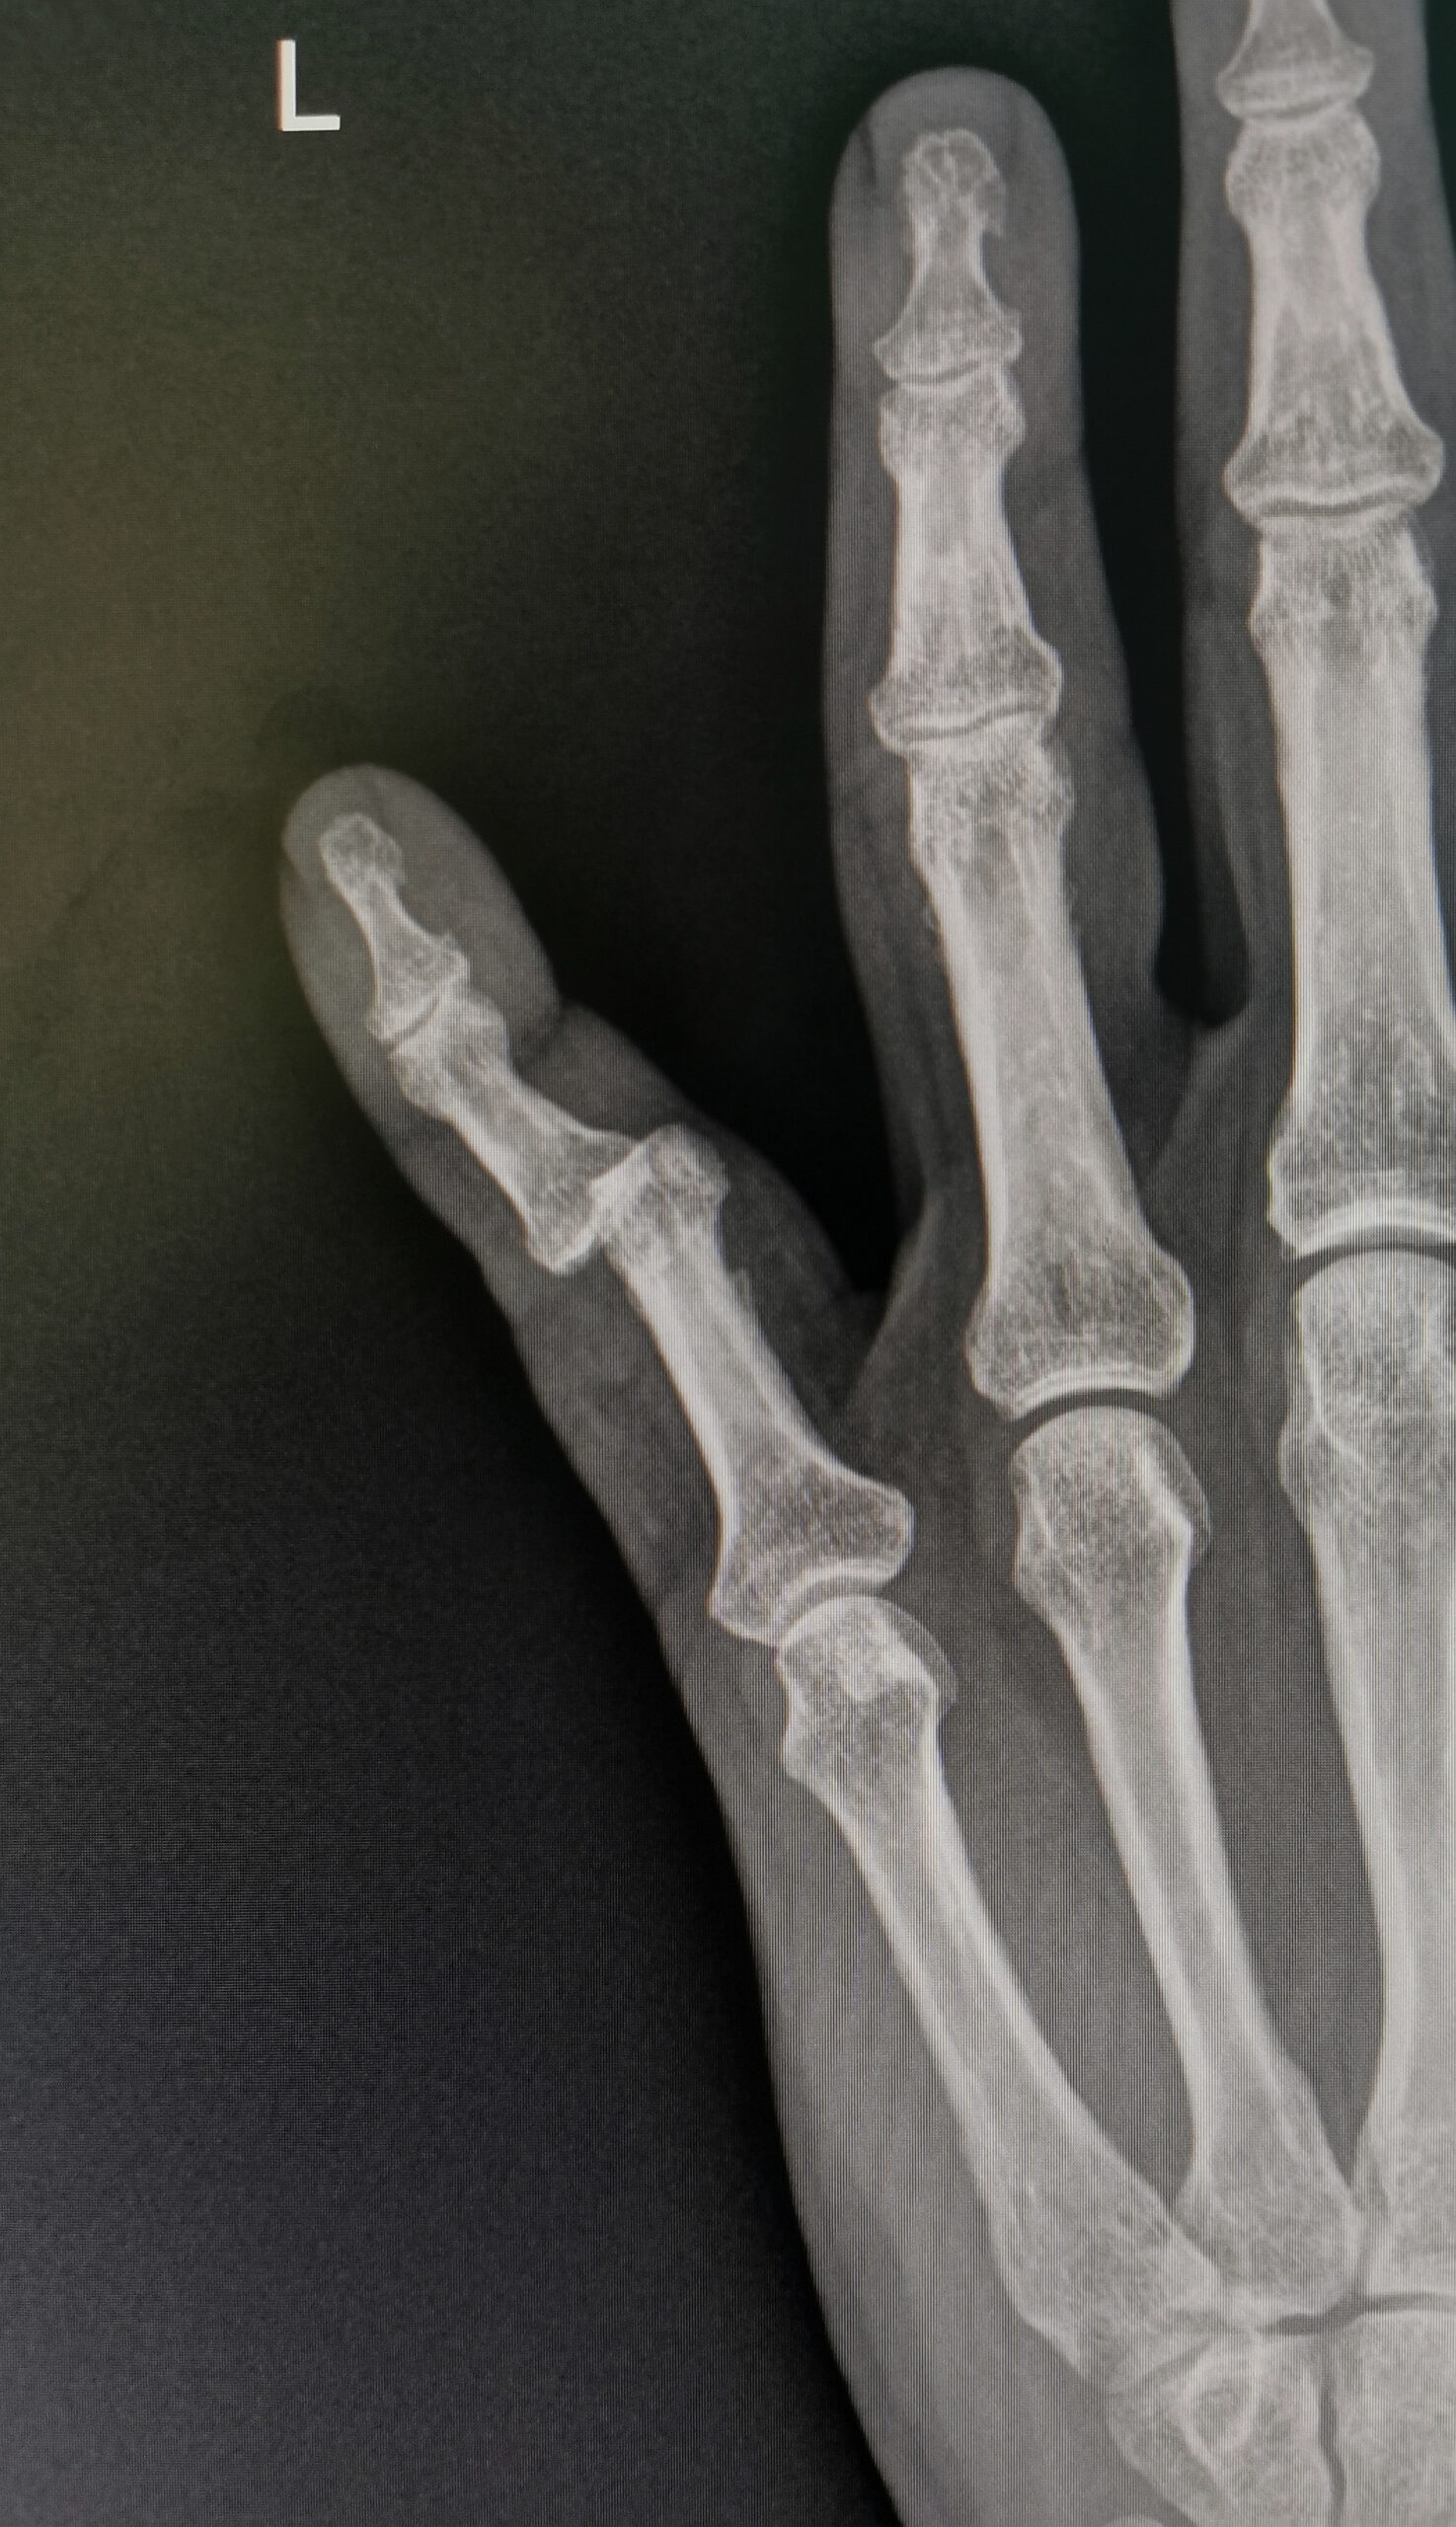

Patients will require x-ray imaging to determine the positioning of the bones after a finger dislocation. If the patient has a displaced fracture, they will benefit from both repositionings of the bones and placement of plates, screws, or pins to put the bone back in place. Some patients will need surgery and pinning of the finger to hold the finger in place even if there isn’t a fracture.

Finger dislocation surgery repairs some finger dislocations. This can happen when a finger’s bone has moved away from its normal position. Finger dislocations can be caused by jamming or overextending the finger during a fall, sports, or as a result of a work injury.